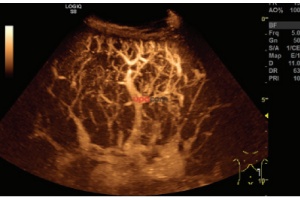

- Система Logiq S8 GE Healtcare, производства Россия – это уникальная ультразвуковая система экспертного класса, компактная и мобильная, удобная в эксплуатации.

- B-режим, M-режим, PW допплер, цветовое допплеровское картирование и энергетический допплер, кодированное излучение, кодированную тканевую гармонику.

- Программа 3D реконструкции для цветового допплеровского картирования и энергетического допплера: